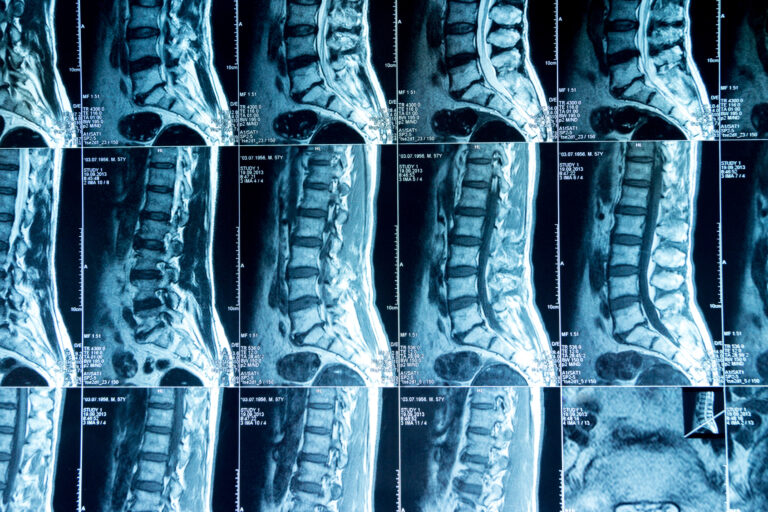

Spinal cord and serious back injuries can be life-altering. A car crash on I-15 near Bear Valley Road, a fall at a Victorville retail center, or an on-the-job accident at a High Desert warehouse can leave you facing chronic pain, limited mobility, or even paralysis. With that said, a skilled Victorville spinal injury lawyer can help you face what comes next.

Understanding the Impact of Spinal Injuries

The spine is one of the body’s most vital and delicate structures. Injuries can range from herniated discs and fractured vertebrae to complete spinal cord damage. Consequences may include: